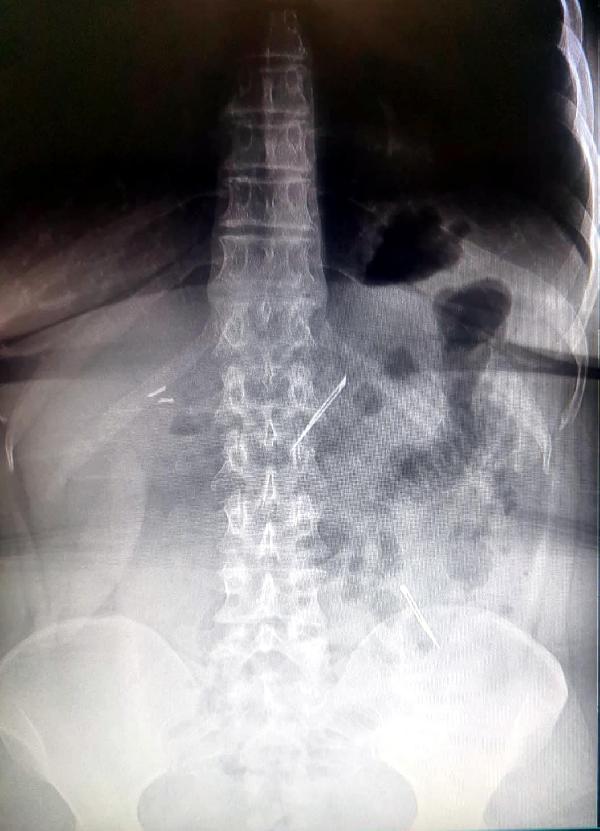

Ankara’da karın ve mide ağrısı şikayetiyle hastaneye başvuran kadın, tedavi altındayken ağrıları artınca hemen ameliyata alındı. 46 yaşındaki kadının ince bağırsak bölgesinden 4 santimlik 2 neşter çıktı.

Sağlık Bilimleri Üniversitesi Ankara Atatürk Sanatoryum Eğitim ve Araştırma Hastanesi'ne 10 gün önce karın ve mide ağrısı şikayetiyle başvuran D.E.’nin (46) yapılan tetkikler ve röntgen çekiminde karnında 2 yabancı cisim tespit edildi.

Hastanede müşahedeye alınan D.E, ağrılarının artması üzerine ameliyata alındı. Ameliyat ile D.E'nin ince bağırsak bölgesindeki 2 cisim çıkarıldı.

Yapılan incelemede cisimlerin 4 santim boyunda, yarım santim eninde neşter olduğu belirlendi.